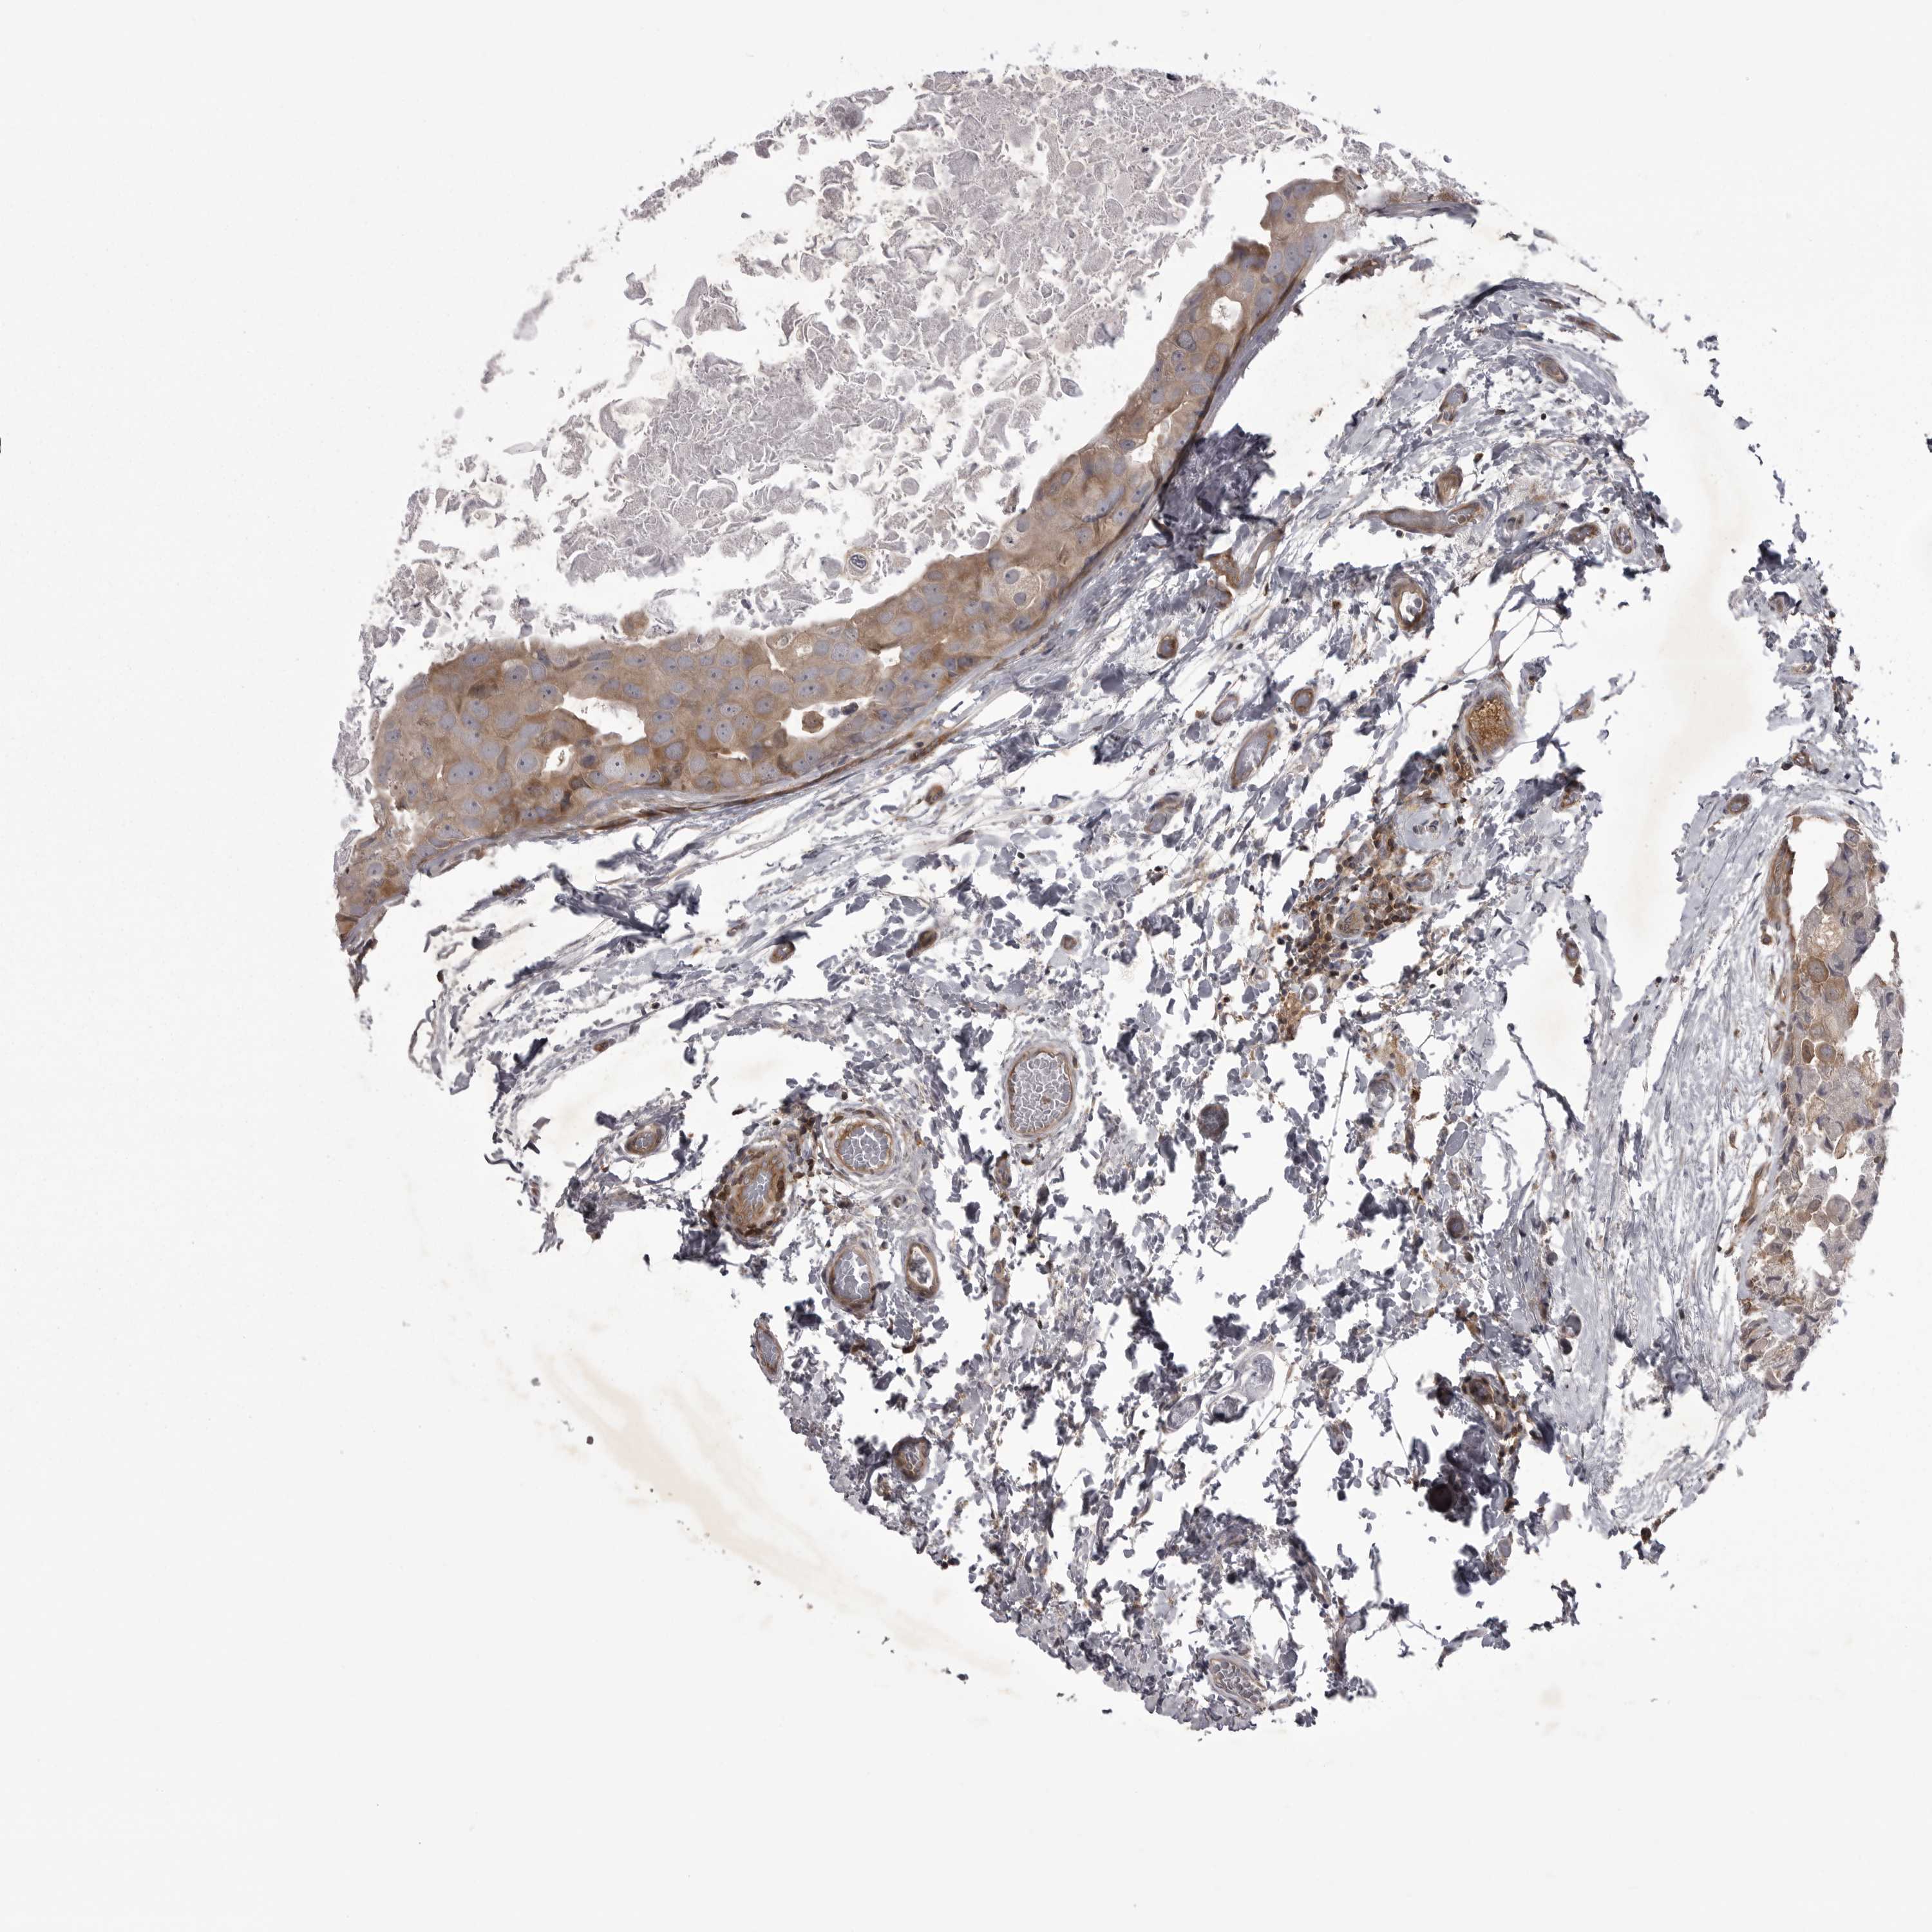

CANCER BREAST CANCER Show tissue menu

BRCA TCGA BRCA VALIDATION PROTEIN EXPRESSION